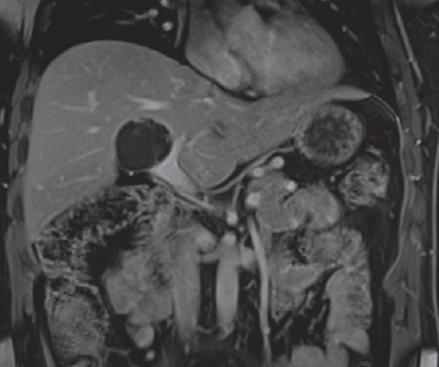

Oliver Daniel Maida Medina, Xavier Ander De Aretxabala Urquiza, Giancarlo Schiappacasse Faúndes, Leonor Adriana Castiblanco Galvis

|